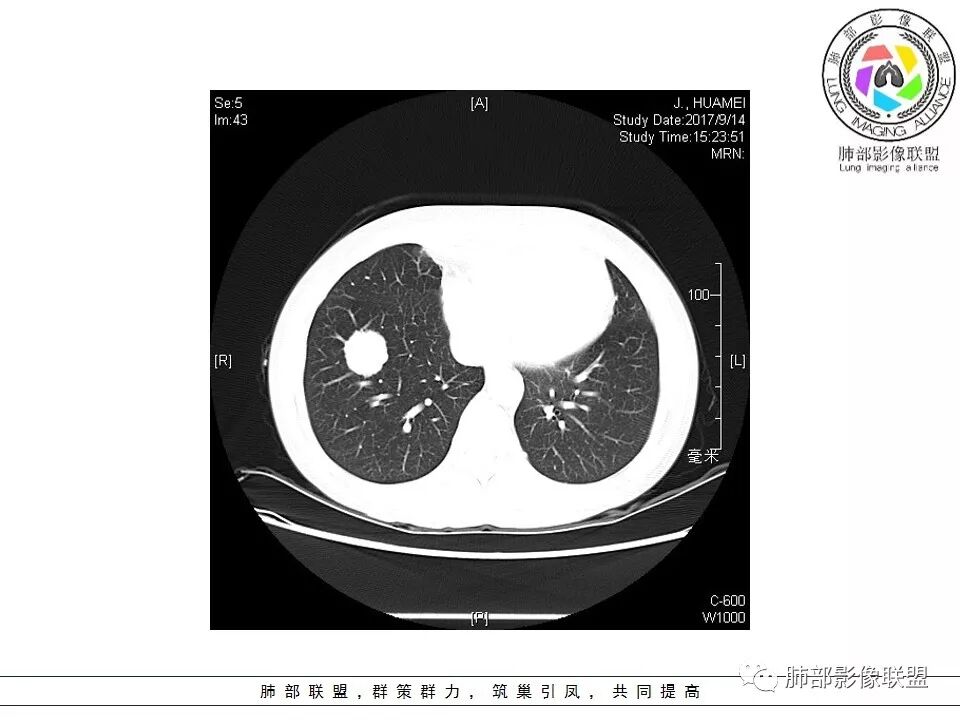

晨读:右肺下叶肿块影,浅分叶,不均匀强化,有血管穿行其中,考虑肺癌,神经内分泌肿瘤可能性大。

右肺下叶结节,边缘毛糙,内支气管推移,有血管贴行,小细胞肺癌?

晨读:右下肺前基底段支气管亚段分叉处占位,密度均匀、中度均匀强化,结节近边缘有支气管、血管穿行,结节边缘较光滑、有细短毛刺、无分叶,结节周围无卫星灶。考虑:PSP,鉴别:小细胞肺癌、不典型错钩瘤

内部支气管扩张,穿行血管形态自然,支持malt。

中央有支气管穿行,PSP排除吧

轻度分叶,支气管穿行,轻中度强化,血管漂浮,考虑MALT

右肺下叶前基底段肿块,边缘不光滑,毛糙,内见充气支气管征,边缘有浅分叶,肿块周围无病灶,排除了结核。增强扫描明显强化,内见血管影,考虑恶性肿瘤。女性,腺癌多见。

淋巴瘤与小细胞癌鉴别,纵隔内没有肿大淋巴结、结节边缘比较毛糙,淋巴瘤放第一位。

病灶呈圆形,轻度分叶,内见血管及支气管影,考虑MALT。

右肺下叶前基底段结节 边缘磨玻璃密度较清 内部支气管扩张,轻中度强化 穿行血管形态自然,支持淋巴瘤。

晨读:右肺下叶肿块影,浅分叶,边界清,轻度均匀强化,血管自然穿行,NSE偏高,考虑小细胞肺癌!

中年女性,右肺下叶前基底段肿块,轻度分叶,有棘样突出,充气支气管征穿行并形成脐凹征。增强扫描中度强化,内见血管影,血管壁毛糙,考虑恶性,腺癌?小细胞肺癌?

晨读,右肺下叶前基底段实性结节,边缘膨隆,可见多发浅分叶,结节内密度均匀,增强后呈轻度均匀强化,血管穿行走形自然,首先考虑恶性肿瘤,内有支气管穿行,淋巴瘤可能大,腺癌待排。

右肺下叶肿块,边缘光滑,浅分叶,膨隆明显,局部有清楚的ggo,考虑恶性,类癌首可能,鉴别腺,PSP。

中年女性,右下类圆形肿块,部分膨胧,边缘浅分叶,脐凹,内见血管穿行,增强轻中度强化,叶间胸膜结节?考虑腺癌,内有支气管穿行,鉴别淋巴瘤。

右肺下叶肿块影,边缘光滑,彭隆,浅分叶,内见支气管通过,增强明显强化,内见血管影,考虑恶性肿瘤,神经内分泌癌,鉴别淋巴瘤。

中年女性,体检发现,病史及化验无特殊。胸部CT右肺下叶前基底段见一类圆形结节,边界清楚,分叶不明显,边缘呈锯齿状改变,病灶内支气管穿行,无扩张及扭曲,增强扫描病灶明显均匀强化,内见穿行血管影,走形无扭曲。考虑粘膜相关性淋巴瘤可能。鉴别炎性假瘤、腺癌及小细胞癌。

右下肺类圆形实形结节,边缘膨隆,浅分叶,其内可见支气管及血管影走行,轻度强化,考虑恶性病灶,淋巴瘤?类癌?

边缘彭隆,还是考虑肿瘤,支气管通入,肺内原发,支气管自然穿行稍扩张,血管比较自然同行,漂浮征,增强后整个比较均匀无明显坏死,淋巴瘤首选。恶性应该没有问题,建议穿刺。